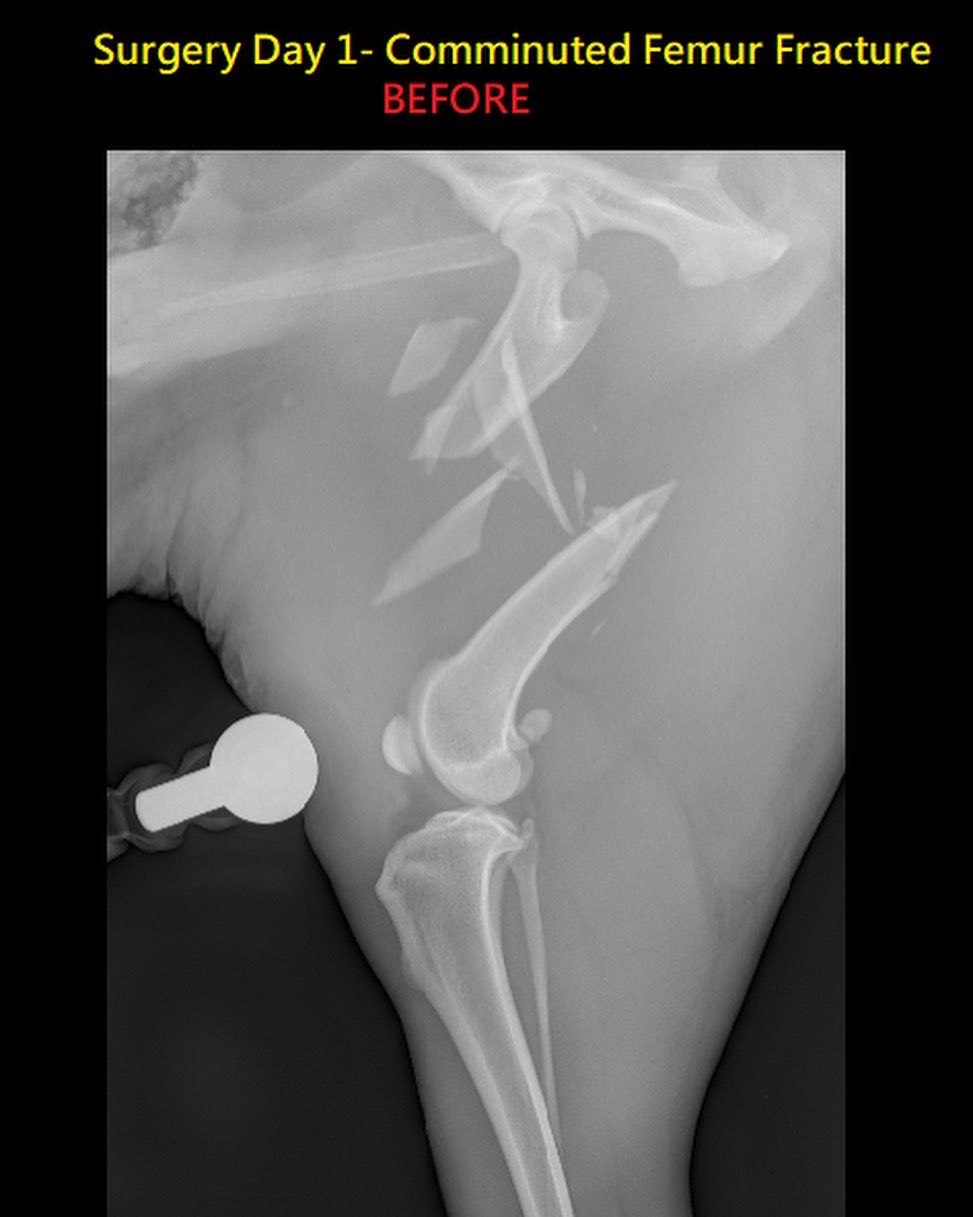

Memphis Veterinary Specialists Memphis Mvs Twitter